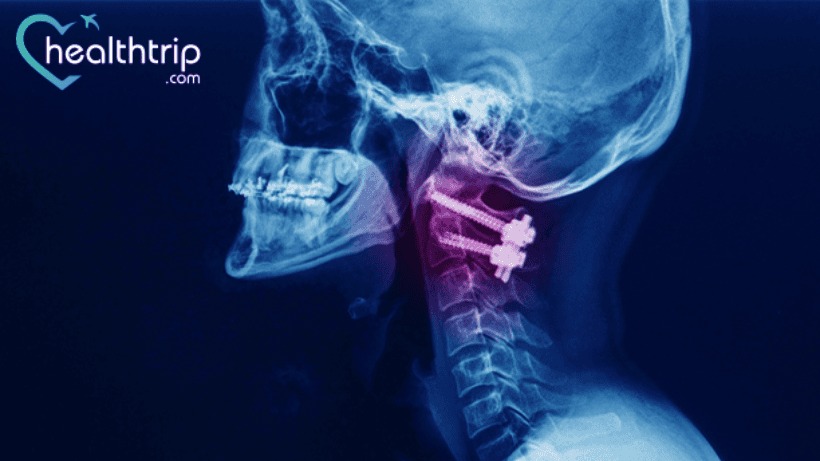

Salah satu operasi fusi tulang belakang yang umum dilakukan adalah Bedah Disektomi dan Fusi Serviks Anterior (ACDF).

Operasi fusi serviks telah sangat berhasil bagi banyak orang. Orang yang tidak mendapatkan hasil yang baik dari operasinya mengalami peningkatan nyeri leher, ketidakstabilan leher, dan taji tulang. Dalam beberapa kasus, mereka juga diberi tahu bahwa diperlukan lebih banyak fusi untuk memperbaiki fusi yang gagal.

Menurut ahli bedah tulang belakang kami, berikut adalah gejala operasi fusi serviks yang gagal:

- Sakit kepala sinus dan masalah postur tubuh setelah operasi: Hal ini mungkin terjadi karena kegagalan perangkat keras atau kerusakan saraf akibat pembedahan. Alasannya harus diselidiki dan dikesampingkan. Setelah itu para ahli kami akan fokus pada segmen leher yang berdekatan untuk melihat apakah fusi tersebut menyebabkan kondisi ketidakstabilan leher yang memburuk atau tidak..

Dalam kasus ini, diperlukan lebih banyak operasi untuk memperbaiki masalah tersebut. Para pasien berhasil menjalani fiksasi atlantoaksial dan C2-C3, dan mereka dapat berjalan mandiri lagi 21 bulan setelah operasi baru.